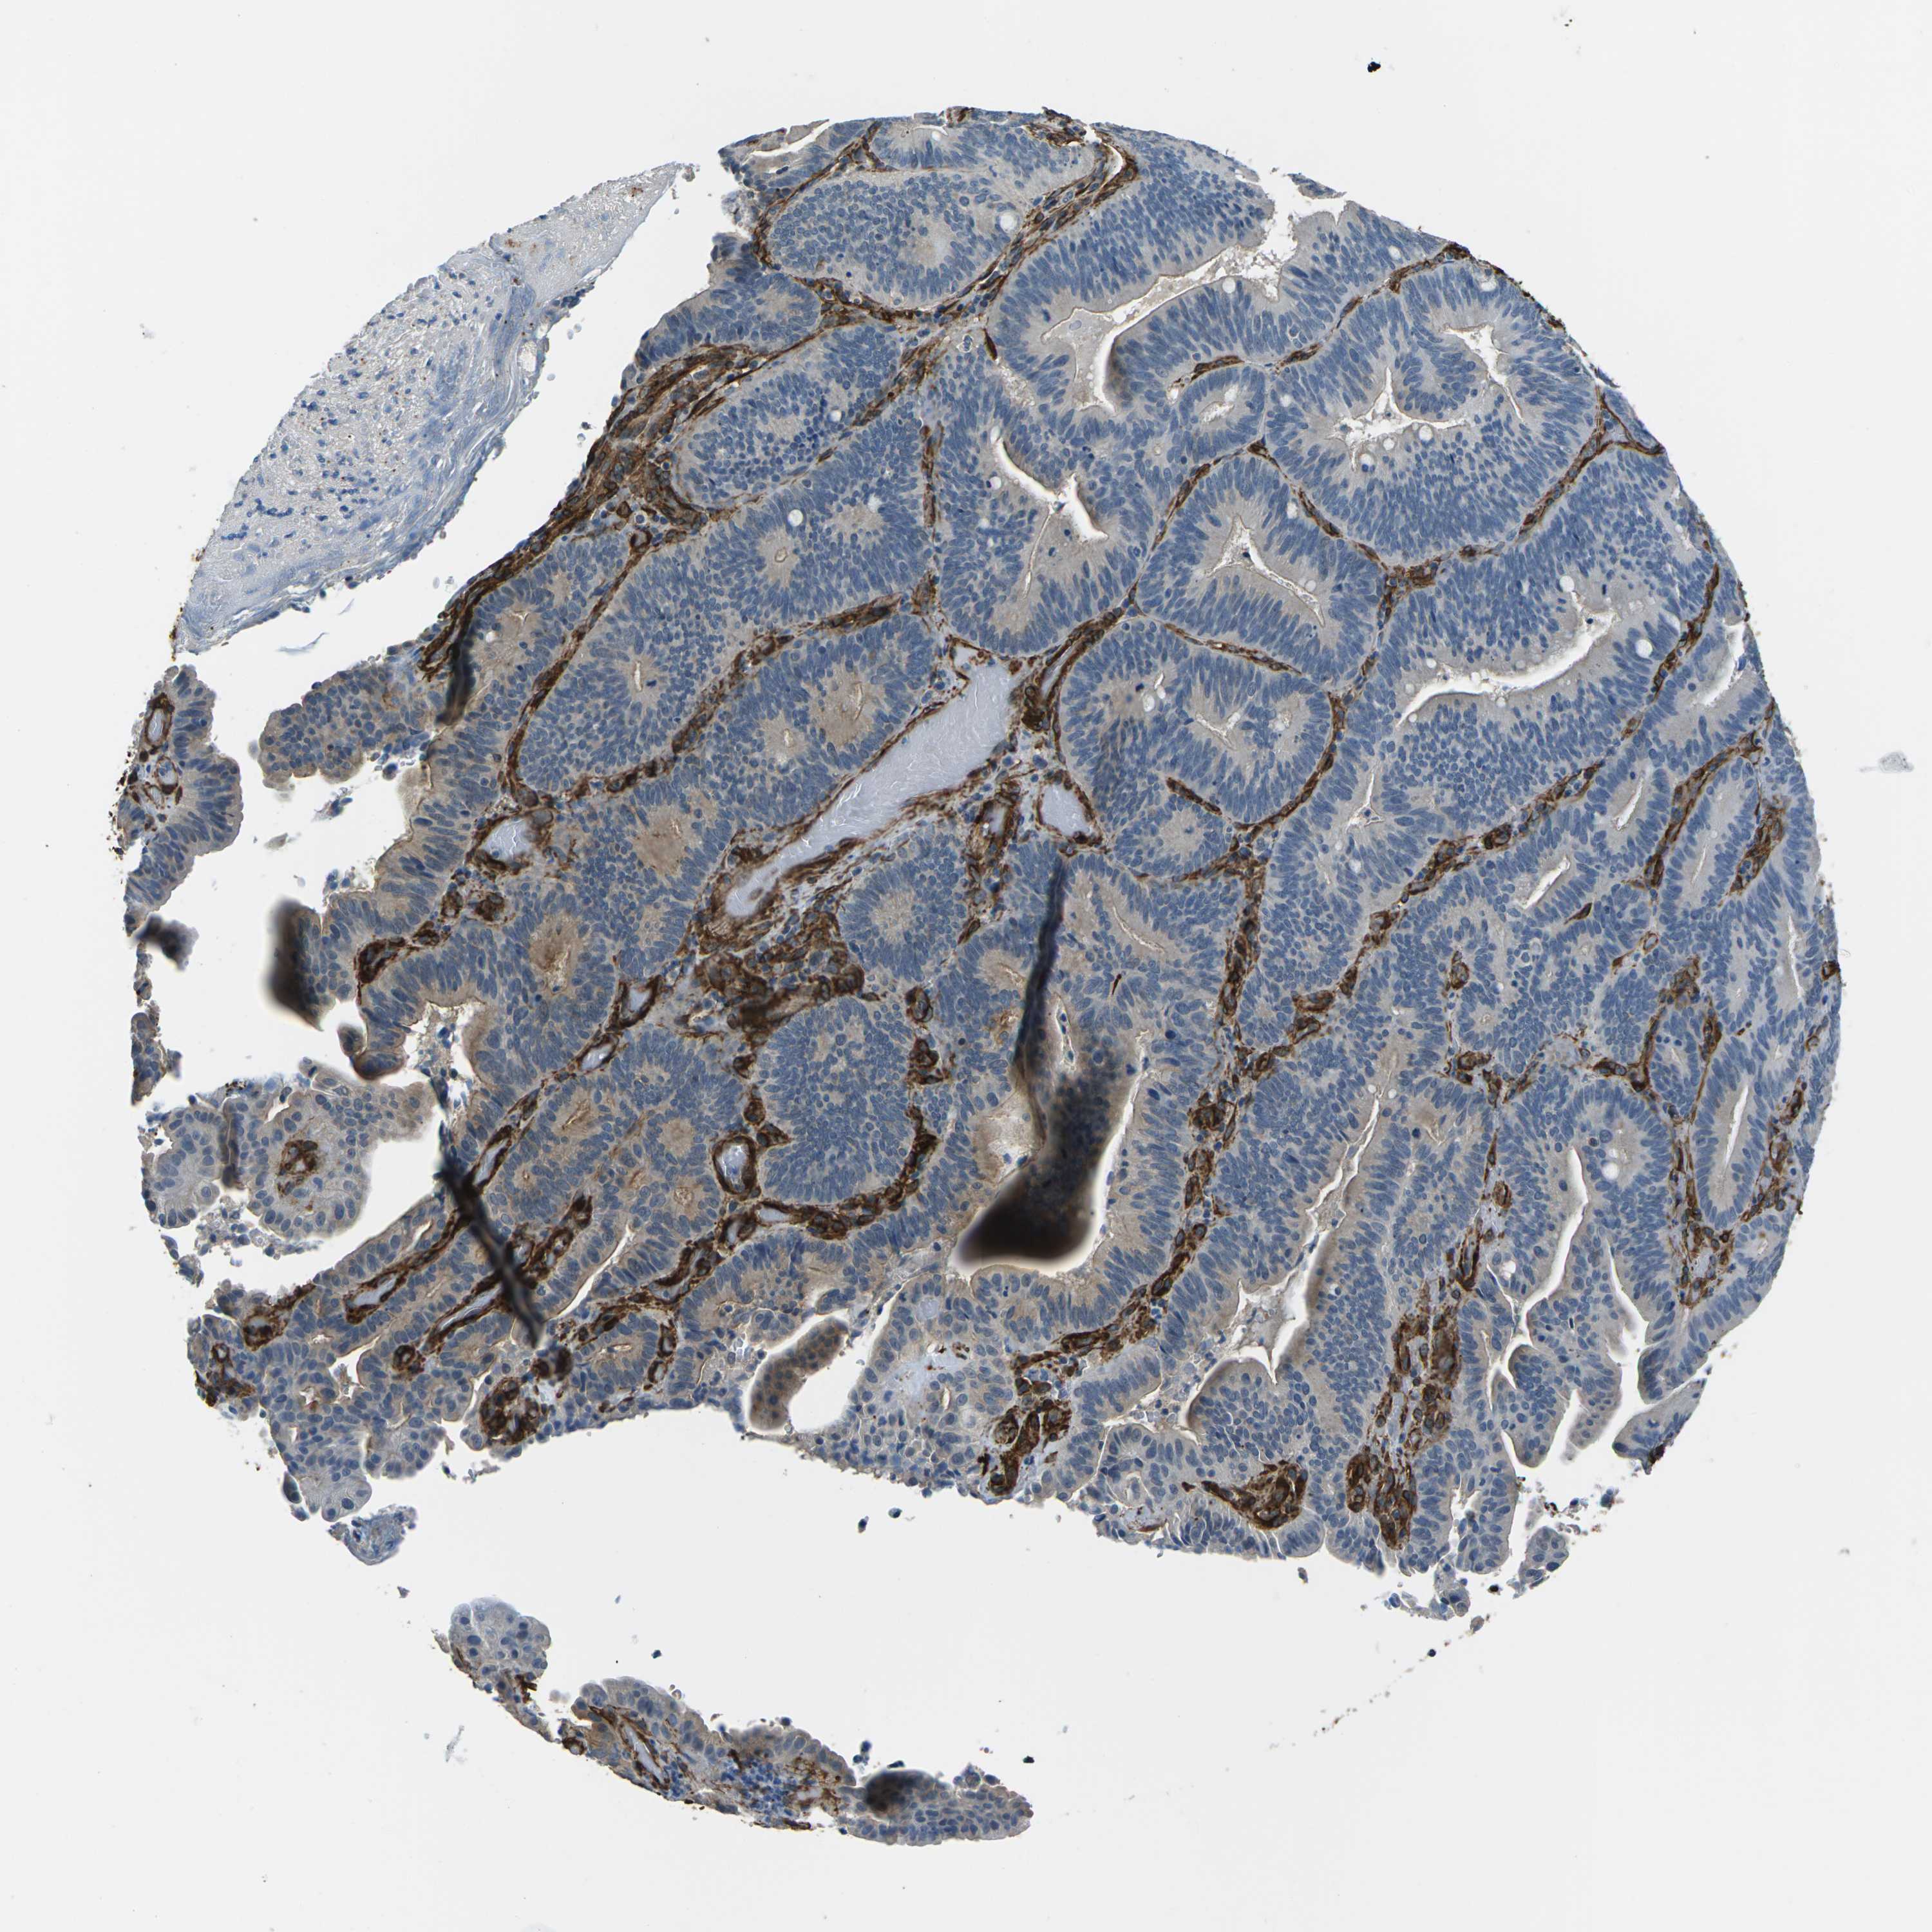

PANCREATIC CANCER - Protein expressioni

A mouse-over function shows sample information and annotation data. Click on an image to view it in a full screen mode. Samples can be filtered based on level of antibody staining by selecting one or several of the following categories: high, medium, low and not detected. The assay and annotation is described here.

Note that samples used for immunohistochemistry by the Human Protein Atlas do not correspond to samples in the TCGA dataset.

Antibody stainingi

Antibody staining in the annotated cell types in the current human tissue is reported as not detected, low, medium, or high, based on conventional immunohistochemistry profiling in selected tissues. This score is based on the combination of the staining intensity and fraction of stained cells.

Each image is clickable and will lead to virtual microscopy that enables deeper exploration of all samples and also displays staining intensity scores, fraction scores and subcellular localization as well as patient and tissue information for each sample.

Antibody HPA012316

Staining

High

Medium

Low

Not detected

Intensity

Strong

Moderate

Weak

Negative

Quantity

>75%

75%-25%

<25%

None

Location

Nuclear

Cytoplasmic/membranous

Cytoplasmic/membranous,nuclear

Adenocarcinoma, NOS

Adenocarcinoma, metastatic, NOS